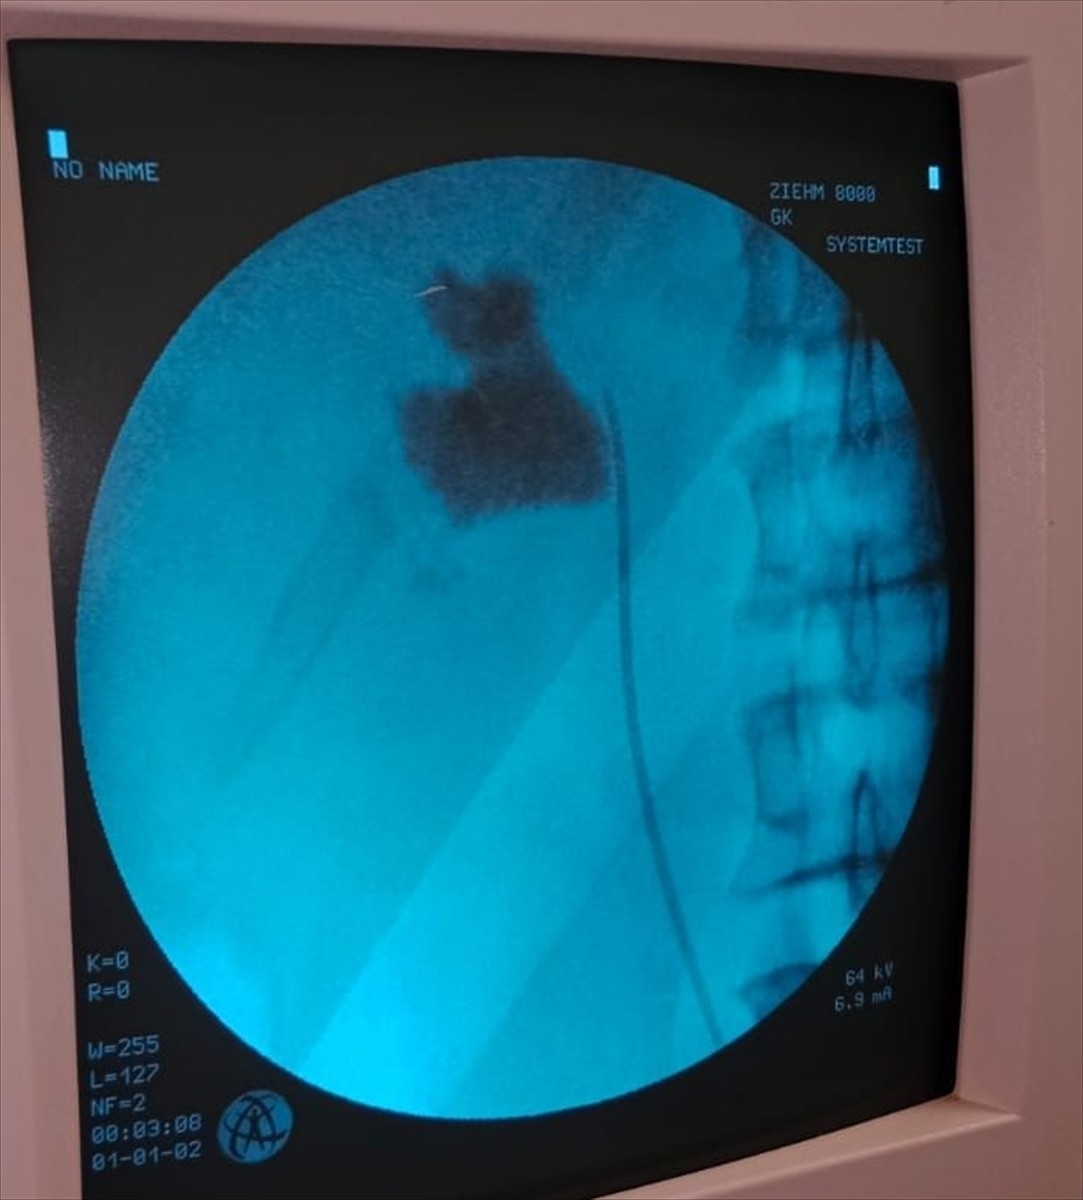

Kırşehir'de bir hastanın böbreğindeki 6 santimetrelik taş kapalı ameliyatla çıkarıldı. Kırşehir Eğitim ve Araştırma Hastanesi'nden yapılan açıklamaya göre, hastaneye başvuran 58 yaşındaki İlhan Çakır'ın kontrollerinde böbreğinde 6 santimetrelik taş tespit edildi.

Üroloji Kliniğinden Uzm. Dr. Talip Göktaş ve ekibi tarafından, kapalı ameliyat yöntemi ile hastanın böbreğindeki taş başarıyla çıkarıldı. Ameliyat sonrası taburcu edilen Çakır, operasyonu gerçekleştiren Göktaş ve ekibine teşekkür etti.

Uzm. Dr. Talip Göktaş, hastanın sol böbreğinde tespit ettikleri 6 santimlik taş için kapalı böbrek taşı çıkarma yöntemi PNL'nin kullanıldığını belirtti ve şu ifadeleri kullandı: "Hastamız 1 gün sonra taburcu edildi. Bu yöntemle hastalarımız açık ameliyatlara göre erken dönemde işlerine dönebiliyor ve daha konforlu bir şekilde ameliyat sürecini atlatabiliyor. 5 yıl içinde hastanemizde 50'den fazla bu tarz ameliyatı başarıyla gerçekleştirdik."